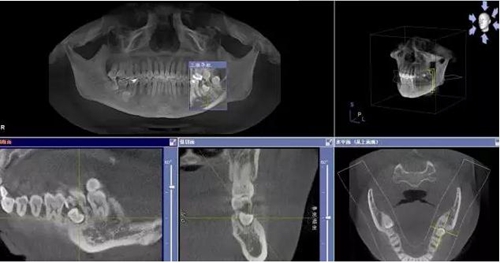

圖1.術(shù)前的CBCT檢查:37頰側(cè)部分牙根被完全壓迫吸收。

1.jpg